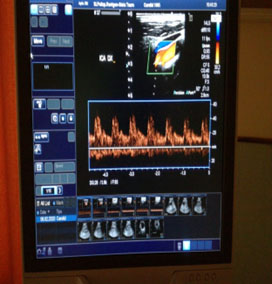

ECOCOLORDOPPLER

Esame non invasivo, indolore,esente da rischi, attraverso il quale è possibile visualizzare la situazione anatomica e funzionale dei vasi sanguigni arteriosi e venosi, studiando il flusso ematico al loro interno.